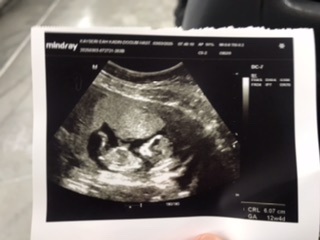

10 hafta 6 günlük bebişim 3 oğlum var tabiki önceliğim sağlıklı olması anlayan varmı çok merak ettım doktor soylemedı şimdiden tşk ederim cevap veren olursa 🥰🥰

Ben kendi bebeğimin cinsiyetini nub teorisine göre tahmin etmiştim ama sizinki çok minik 🥰 2 hafta sonra olsaydı belki anlaşılırdı. Şu görünen kemik düz olduğunda kız, yukarı doğru eğik olduğunda erkek diyorlar